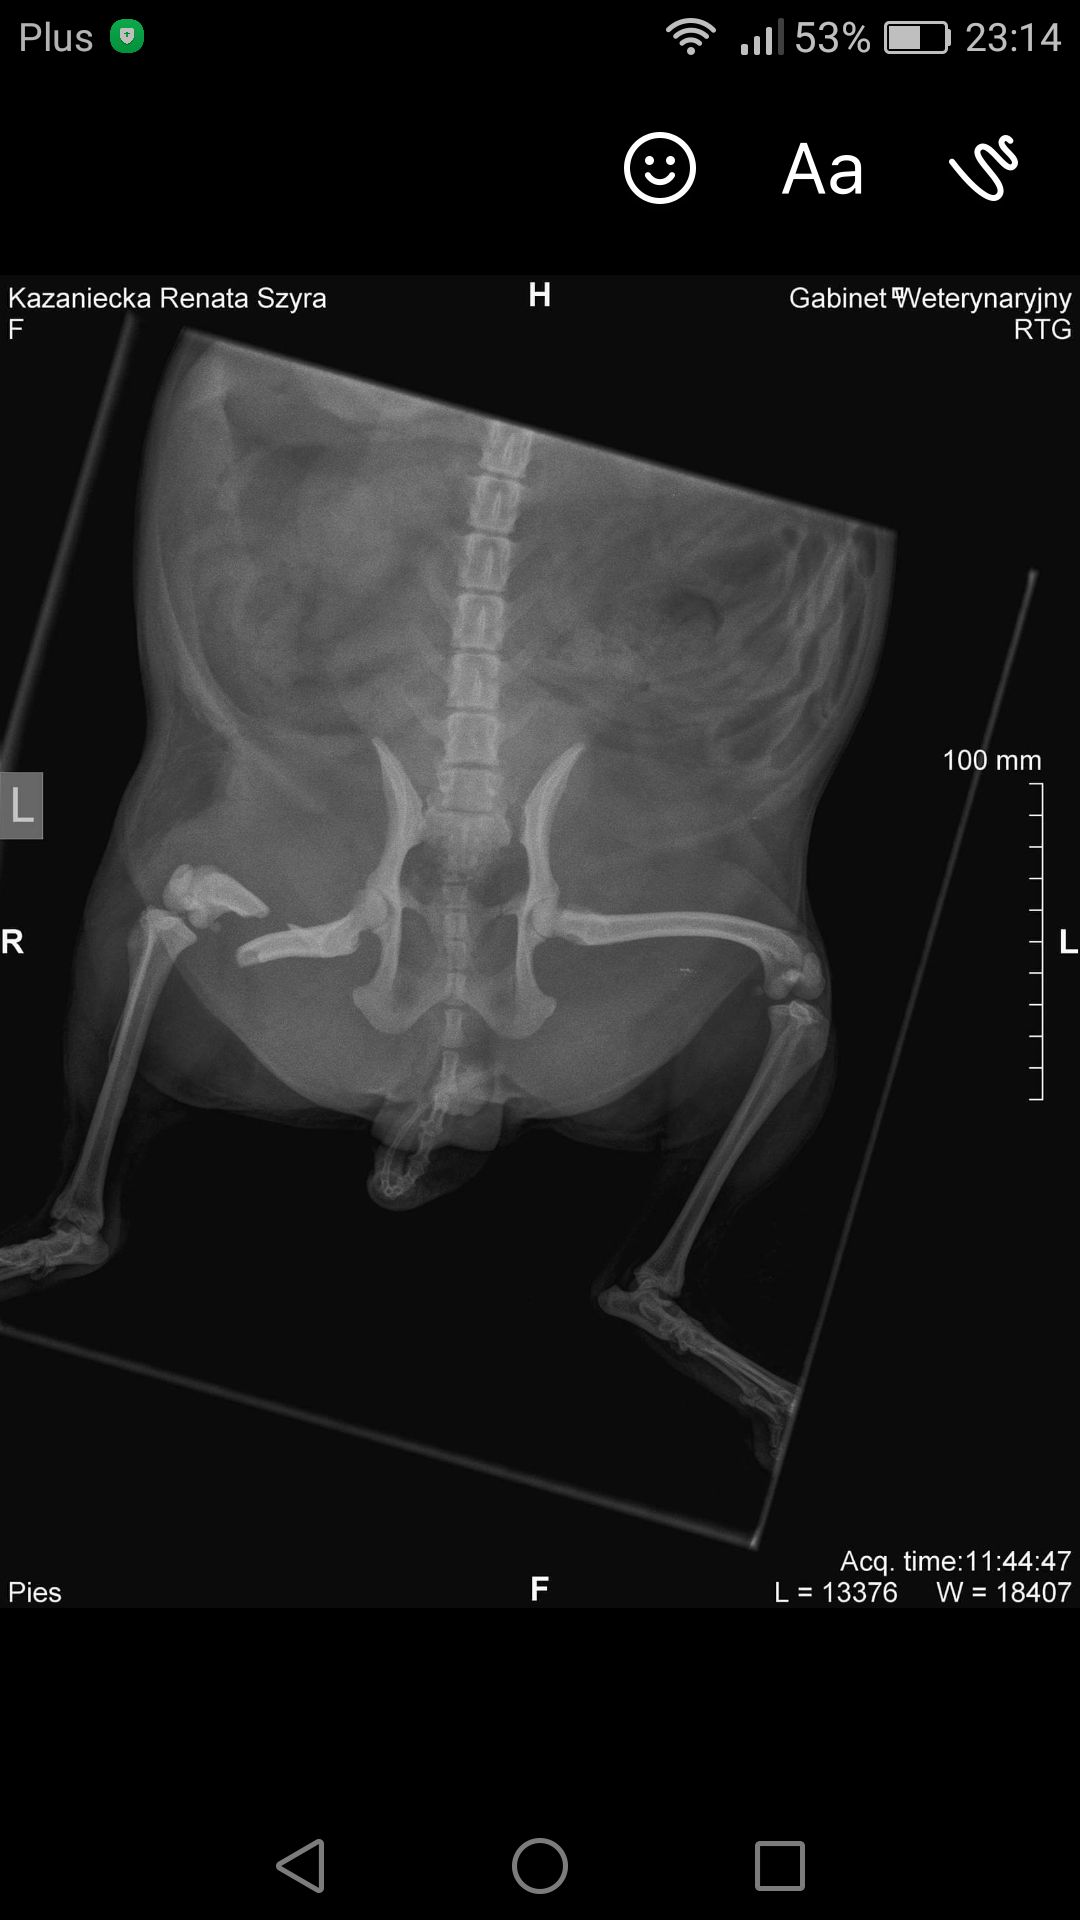

Pomóż uratować Szyrę dorzucając grosik na operację!

Szyra wpadła pod samochód, ma złamaną kość udową. Psiak nie może chodzić i cierpi z bólu. Potrzebuje natychmiastowej operacji, która jest jednak bardzo kosztowna.

Operacja, która uratowałaby życie i zdrowie suni, jest skomplikowana i bardzo droga, jej koszt to ok. 1000 zł. Potrzeba też pieniędzy na leki, rehabilitację i transport/dojazdy do Szczecina, gdzie znajduje się najbliższa klinika, która mogłaby wykonać operację.

Operacja, która uratowałaby życie i zdrowie suni, jest skomplikowana i bardzo droga, jej koszt to ok. 1000 zł. Potrzeba też pieniędzy na leki, rehabilitację i transport/dojazdy do Szczecina, gdzie znajduje się najbliższa klinika, która mogłaby wykonać operację.